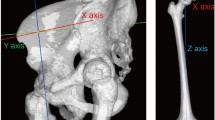

A MB model of the left lower limb (Fig. 2) was developed using Adams software 2017 (MSC Software Corporation, Santa Ana, USA) to estimate the hip contact force (HCF) and contact point location during a normal walking task. The model comprises bony geometries from the pelvis to the tibia, major hip muscles, and a parametrized hip prosthesis.

In detail, standardized bone geometries (Sawbones Europe AB, Malmoe, Sweden) were scaled according to data of an average patient from the OrthoLoad dataset with a body weight (BW) of 836 N44. In addition, the patella was represented by an ellipsoid with congruent dimensions. The femur and tibia masses were computed as percentage of the total BW, resulting in 8.9 kg (10.5%) and 3.8 kg (4.5%) for femur and tibia, respectively45. The parametrized hip prosthesis comprises a cylinder representing the implant neck, extending from the osteotomy level to the center of the femoral head. The femoral head is modeled as a sphere centered within a simplified acetabular cup, which, in turn, is represented as a hollow hemisphere rigidly fixed to the pelvis. Thus, a contact pair was defined at the hip joint, modeled using an impact formulation37 with a contact stiffness of 2.7 × 106 N/mm1.5 calculated based on the Hertzian theory, considering the material properties (Table 1) of a femoral head of zirconia-toughened alumina (ZTA) and an acetabular cup of ultra-high molecular weight polyethylene (UHMWPE). Based on this formulation, the contact point is defined as the centroid of the intersecting volume between the undeformed shapes of the head and the acetabular cup, which compenetrate during the contact phase.

Concerning the knee joint, a one-degree-of-freedom (DoF) hinge joint was employed, with the patella constrained to move, together with the tibia, along a circular pathway around the intercondylar axis, which was defined as the axis passing through the centers of two ellipsoids inscribing the femoral condyles.

The major muscles crossing the hip joint (Supplementary Table S1) were included in the model with origin and insertion attachment points adapted from the ‘Gait2392’ model provided by the OpenSim software47. Each muscle bundle was implemented as an actuator applying traction force between the origin and insertion points, and via-points were added to account for non-linear muscle paths (e.g., gluteal muscles). Furthermore, a torque actuator located at the knee joint was used to compensate for the absence of the gastrocnemius muscle and its contribution to knee flexion.

Overall, the MB analysis involved two sequential steps. Briefly, first, an inverse kinematics of 1.1 s was carried out where the motion is prescribed to the body segments of the model by using a set of motion agents each consisting of a body-fixed marker coupled, through a bushing element, to a target driven by markers’ trajectories obtained via motion capture of a normal walking task44 (Fig. 2). Secondly, the resulting muscle lengthening was recorded and used as input to a muscle-driven forward dynamic simulation, where external forces and torques are directly applied to the ankle joint while the pelvis kinematics was prescribed. The muscle action, required to reproduce the previously recorded muscle lengthening patterns, was computed by feedback controllers and limiting the generated force to the maximum isometric force (Supplementary Table S1) of each muscle47,48,49,50.Finally, the two-step MB analysis was repeated by varying the prosthesis neck length, head size, or both of them as previously described. In particular, in the MB framework, the head size variation turns out in a moment arm change obtained by moving a defined fixed head-neck joint along the neck axis. Thus, the resultant HCF and contact location with respect to a local reference system centered on the femoral head were computed. After filtering in Matlab R2021b (MathWorks, Natick, Massachusetts, USA) by using a fourth-order low-pass Butterworth filter with a cut-off frequency of 10 and 30 Hz for contact force and contact location, respectively, the derived data were compared and used as boundary conditions for subsequent FE models of the taper junction.